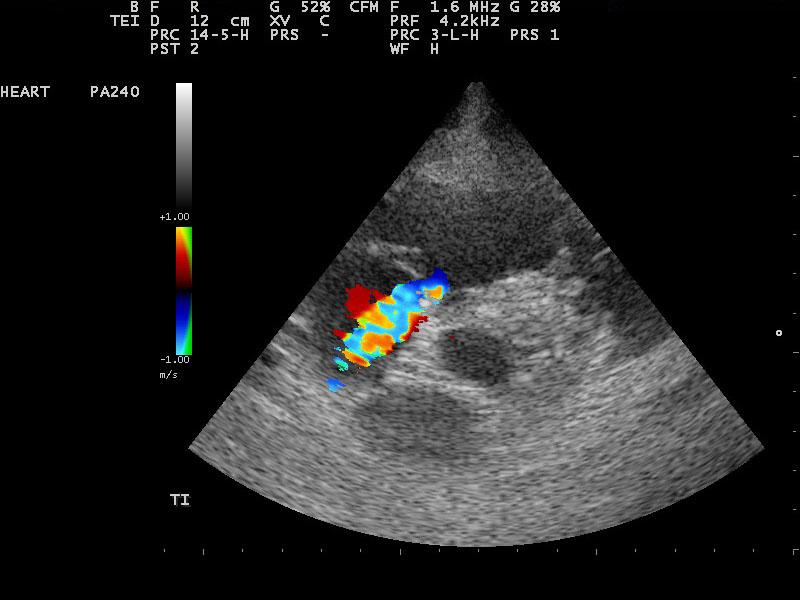

A 10-year-old SF Labrador was presented for evaluation of ascites, which was quantified as a modified transudate. Additional history on this dog was that 11 months prior an ovariohysterectomy and resection of mammary gland tumors had been done. The tumors were benign on histopathology. On abdominal ultrasound, the ascites, hepatic congestion, and a dilated CVC were present.